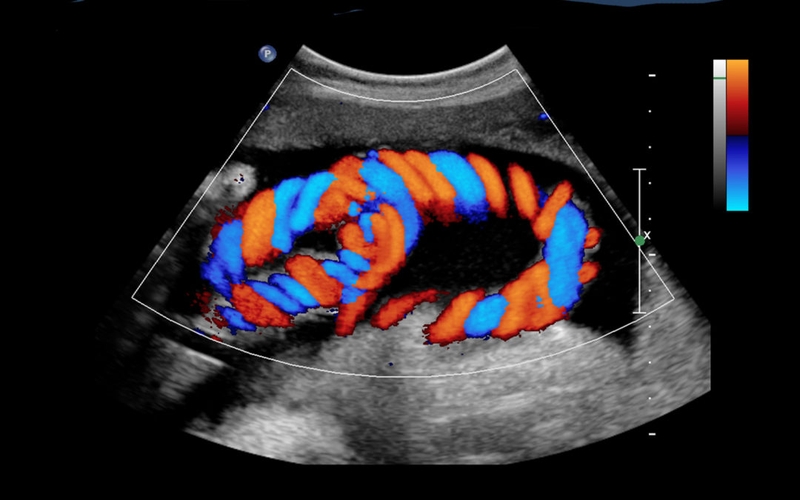

Trước khi tìm hiểu trường hợp cần siêu âm Doppler thai 32 tuần, bạn cũng cần nắm rõ thế nào là siêu âm Doppler. Trong các hình thức siêu âm thai nhi thì siêu âm Doppler là loại được đánh giá cao nhất về tính chính xác, hình ảnh siêu âm dễ quan sát, tương đối rõ ràng vì có màu sắc.

Mẹ bầu được chỉ định tiến hành siêu âm Doppler để đo lượng máu, sinh dưỡng cũng như oxy từ bộ phận của thai nhi. Thông qua kết quả siêu âm Doppler, bác sĩ có thể sớm phát hiện tình trạng sức khỏe và sự phát triển của thai nhi. Trong trường hợp có dấu hiệu bất thường, bác sĩ sẽ kịp thời thông báo, xử lý vấn đề của thai nhi.